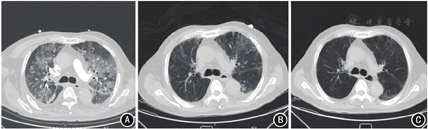

入院体检:体温38.6 ℃,心率70次/min,呼吸20次/min,血压132/78 mmHg(1 mmHg=0.133 kPa)。胸背部皮肤可见多处散在色素沉着,无皮疹及脱屑;口唇无紫绀,呼吸节律正常,双肺呼吸音粗,可闻及散在湿性啰音;心律齐,各瓣膜听诊区未闻及病理性杂音;腹部平坦,脐上可见长约8 cm纵行手术瘢痕,左上腹可见空肠造瘘管,腹部柔软无压痛,肝脾肋下未触及,余未见异常。实验室检查:白细胞计数(white blood cell,WBC)5.6×109/L,中性粒细胞0.89,嗜酸粒细胞0.005;C反应蛋白(C-reactive protein,CRP)110.4 mg/L,降钙素原(procalcitonin,PCT)4.91 μg/L;丙氨酸转氨酶(alanine aminotransferase,ALT)25 U/L,天冬氨酸转氨酶(aspartate aminotransferase,AST)39 U/L,总胆红素(total bilirubin,TBil)19.7 μmol/L,γ-谷氨酰转肽酶(γ-glutamyl transpeptidase,γ-GT)107 U/L,白蛋白25.5 g/L。胸腹部CT示双肺多发斑片影,胆囊炎。入院诊断:(1)胃腺癌(腹腔淋巴结转移、锁骨上淋巴结转移、侵犯胰腺及肝脏,T4N3M1 Ⅳ期);(2)肺部感染;(3)胆囊炎;(4)冠状动脉粥样硬化性心脏病。入院当日予哌拉西林钠他唑巴坦钠4.5 g静脉滴注、1次/8 h。入院第2天,患者出现明显胸闷、憋气,频繁咳嗽,咳出少量暗红色血性痰,体温正常。面罩吸氧(10 L/min)时脉搏血氧饱和度0.93,血气分析示pH 7.4,动脉血氧分压60 mmHg,动脉血二氧化碳分压32 mmHg,氧合指数(动脉血氧分压/吸入氧浓度)100 mmHg(参考值:400~500 mmHg);WBC 6.1×109/L,中性粒细胞0.91,嗜酸粒细胞0.003;CRP 162.4 mg/L,PCT 4.11 μg/L;B型钠尿肽168.5 ng/L,肌钙蛋白I 0.03 μg/L,D-二聚体2.88 mg/L。CT肺血管造影示双肺广泛磨玻璃样渗出,双侧胸腔积液(图1 A)。立即给予无创呼吸机辅助呼吸,转入重症医学科。转科后给予经鼻高流量氧疗(氧浓度55%,流量40 L/min),脉搏血氧饱和度0.96。根据患者病史及肺部影像学表现考虑为纳武利尤单抗所致免疫相关性肺炎,给予甲泼尼龙琥珀酸钠40 mg静脉注射、2次/d,氧驱雾化吸入性布地奈德混悬液(1 mg、3次/d)、乙酰半胱氨酸溶液(0.3 g、2次/d)。因患者有胆囊炎,且不能排除肺部细菌感染及肺孢子菌感染,在继续哌拉西林钠他唑巴坦钠治疗的基础上,加用卡泊芬净静脉滴注(首剂量70 mg,维持剂量50 mg/d)和复方新诺明5片口服、1次/6 h。12月12日,痰细菌培养回报肺炎克雷伯杆菌阳性,曲霉菌甘露聚糖检测阴性,真菌D-葡聚糖检测阳性。12月13日痰液病原体高通量测序示主要病原体为肺炎克雷伯杆菌、鲍曼不动杆菌、白色念珠菌及人类疱疹病毒4型。治疗4 d后,患者自觉喘憋较前明显减轻,血气分析(氧浓度50%,流量40 L/min)示氧分压113 mmHg,氧合指数226 mmHg;WBC 8.0×109/L,中性粒细胞0.87,CRP 4.4 mg/L,PCT 0.31 μg/L,B型钠尿肽114.3 ng/L。排除肺孢子菌感染可能,停用复方新诺明。12月17日,患者体温正常,咳嗽明显减轻,痰量减少,痰中带有少量暗红色血,血气分析(氧浓度35%,流量30 L/min)示氧分压85 mmHg,氧合指数242 mmHg,改为鼻导管吸氧(3 L/min)。胸部CT示双肺见网格样影、磨玻璃影及索条影,呈间质性改变,较前明显好转(图1 B)。12月21日,患者咳嗽及喘憋症状消失,血气分析(鼻导管3 L/min)示氧分压102 mmHg,氧合指数309 mmHg。当日停用卡泊芬净及哌拉西林钠他唑巴坦钠。12月24日,患者好转出院,停用甲泼尼龙琥珀酸钠,改为甲泼尼龙80 mg/d口服。2022年1月5日门诊随访,胸部CT示双肺网格及磨玻璃影,较前好转(图1 C),甲泼尼龙减量为40 mg/d口服,持续7 d后减量为20 mg/d,再7 d后改为8 mg/d。1月22日门诊随访,胸部CT较前无明显变化,停用糖皮质激素。患者后续未再行抗肿瘤治疗,2月5日因急性消化道出血合并肝衰竭死亡。